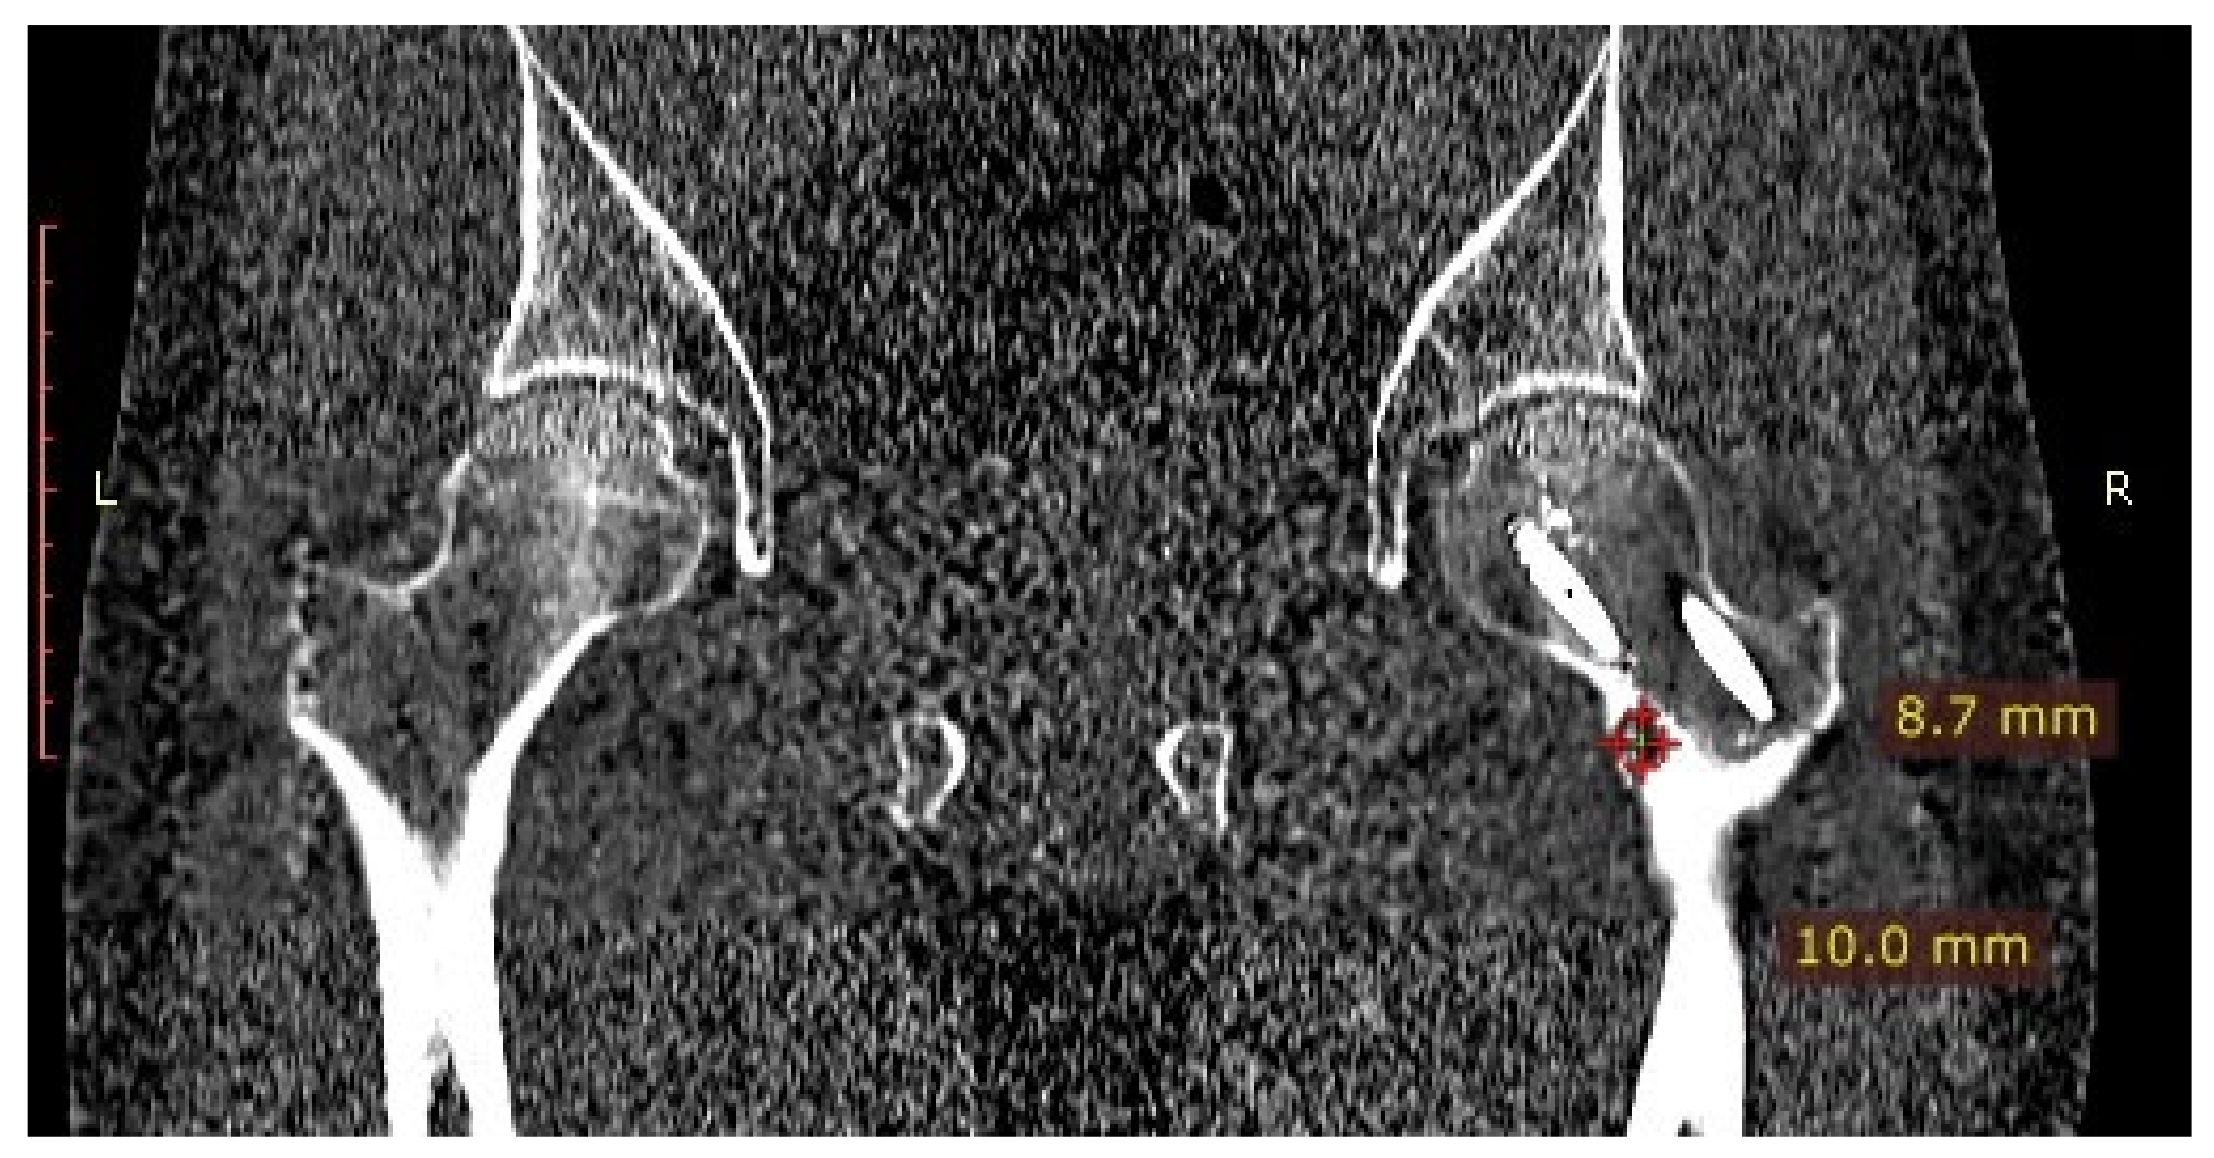

3.1. Case 1: OO Masking as Femoroacetabular Impingement (FAI)